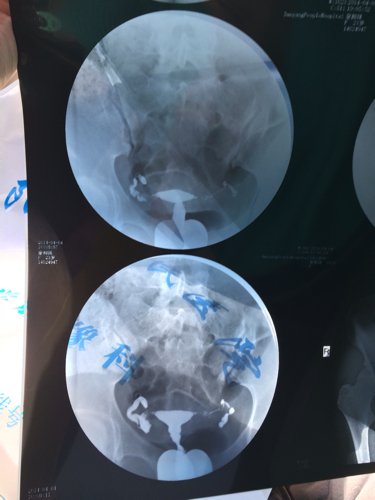

您好,医生。昨天我去做了一个子宫输卵管造影,结果检查所见子宫形态无明显异常。双侧输卵管伞部显影,双侧输卵管呈迂曲柔软的条状影。24小时后摄片示,造影剂在盆腔内积聚,弥散不良。检查结论双侧输卵管伞部碘油积聚,弥散不良,提示双侧输卵管伞部梗阻。请问医生我该怎么治疗,还有没有机会会人工受孕怀个健康宝宝呢?